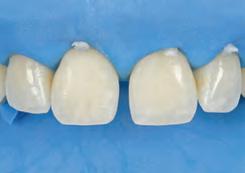

After developing the simulated mock-up, a 3D-printed resin model was created using CAD software (Fig 4a), and a clear PVS matrix (Exaclear, GC America) was fabricated to replicate the printed diagnostic wax-up using a nonperforated tray (Fig

Fig 4 (left) A 3D-printed resin model was created using CAD software. (right) A clear PVS matrix (Exaclear, GC America) was fabricated to replicate the printed diagnostic wax-up using a nonperforated tray.